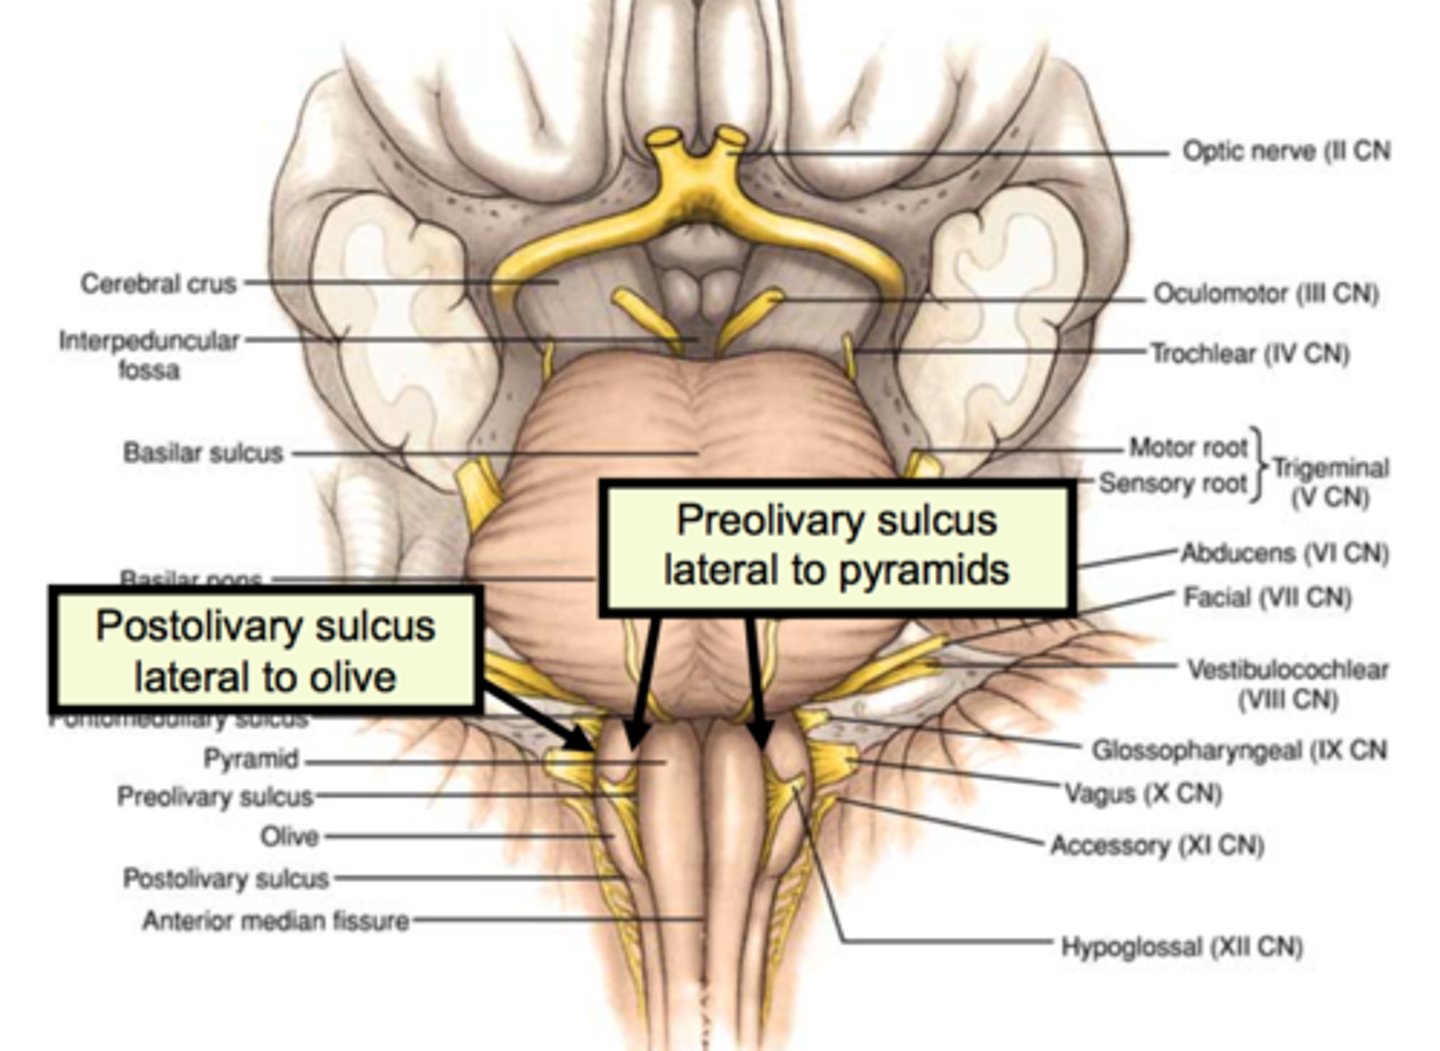

two ridges of tissue on the ventral aspect of the medulla, separated from each other by the ventral median fissure

pyramids

area where most corticospinal fibers decussate over the lower medulla, therefore obscuring the ventral median fissure

pyramidal decussation

elongated mounds of tissue lateral to the medullary pyramids

olives

vertical groove dorsolateral to the inferior olive on each side that gives rise to CN IX and X

postolivary sulcus

Which cranial nerves arise from the medulla? (and pontomedullary junction)

6-10, 12

What is the superior boundary of the pons?

isthmus of the brain stem (between pons and cerebral peduncles)

What is the inferior boundary of the pons?

pontomedullary junction

refers to the large round protuberance on the ventral pons that represents a "bridge" of horizontally oriented fibers connecting the right and left sides

basilar portion

longitudinal midline groove of the pons that is the superior continuation of the ventral median sulcus/fissure, containing a namesake artery

basilar sulcus

white matter stalks that connect the pons to the cerebellum

middle cerebellar peduncles

What is the only cranial nerve that attaches to the pons?

CN V